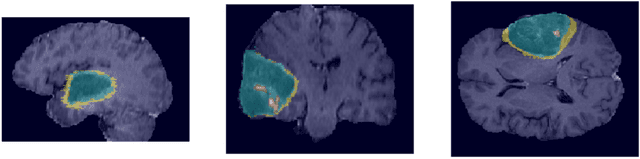

Abstract:We propose a 3D volume-to-volume Generative Adversarial Network (GAN) for segmentation of brain tumours. The proposed model, called Vox2Vox, generates segmentations from multi-channel 3D MR images. The best results are obtained when the generator loss (a 3D U-Net) is weighted 5 times higher compared to the discriminator loss (a 3D GAN). For the BraTS 2018 training set we obtain (after ensembling 5 models) the following dice scores and Hausdorff 95 percentile distances: 90.66%, 82.54%, 78.71%, and 4.04 mm, 6.07 mm, 5.00 mm, for whole tumour, core tumour and enhancing tumour respectively. The proposed model is shown to compare favorably to the winners of the BraTS 2018 challenge, but a direct comparison is not possible.